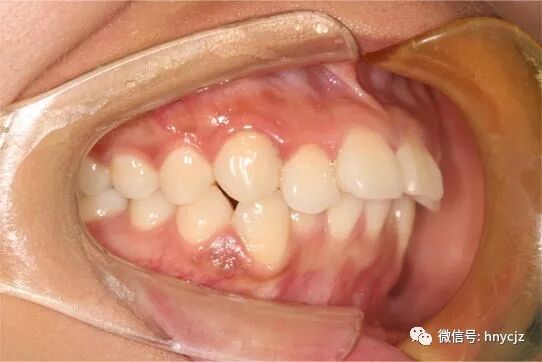

上牙其实我的面型有点微凸,看上面那张上牙的门牙那几颗有一丢丢龅牙,借用崔医生的医生专业术语属于前牙深覆颌,